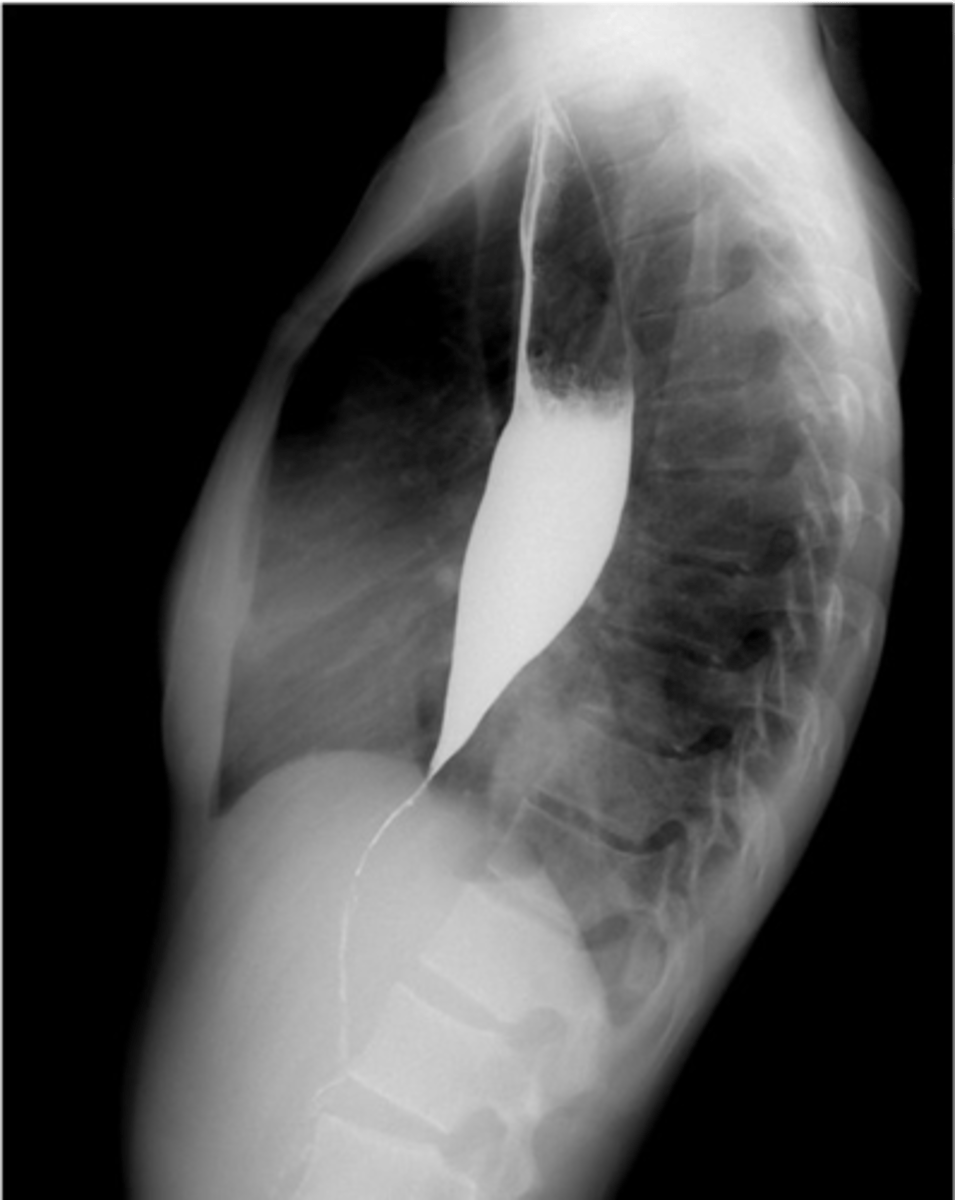

What is Achalasia?

-disease of lower esophageal body and sphincter

-sphincter fails to relax and open to let food pass

-caused by loss of inhibitory neurons in esophagus

-Sx: difficulty swallowing, chest pain, regurgitation

-complications: lung problems, loss of weight

-Dx: XR, endoscopy, esophageal manometry

What does achalsia look like on XR?

-birds beak